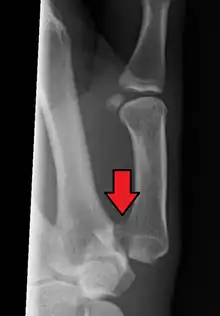

| Bennett fracture on x-ray | |

Bennett fracture is a type of partial broken finger involving the base of the thumb, and extends into the carpometacarpal (CMC) joint.[1]

This intra-articular fracture is the most common type of fracture of the thumb, and is nearly always accompanied by some degree of subluxation or frank dislocation of the carpometacarpal joint.